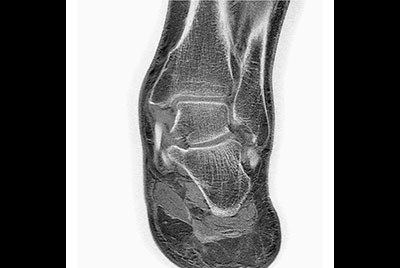

High resolution Ankle imaging in short scan times